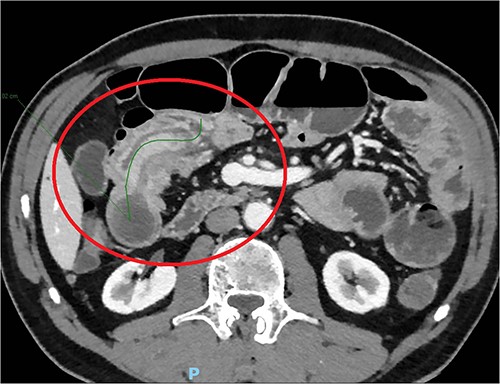

The day after, the new abdominal X-ray documented increasing distension of the bowel, with multiple hydro-aerial levels and it was decided to perform an abdominal CT scan with iodinated contrast agent: this revealed an ileo-ileal invagination extending in the mesogastrium region for about 10 cm, without showing the characteristics of expansive neoformations (Fig. 1).

The laboratory exams showed only mild neutrophilic leukocytosis, without increased inflammatory indexes. The patient was finally admitted to the surgical department for urgent laparotomy and the intraoperative findings revealed an intussusception involving a stretch of about 10 cm and supported by a 4 cm thick, rounded tense-elastic neoformation, possibly originated from the intestinal wall. A segmental jejunal resection and side-to-side mechanical anastomosis were performed.